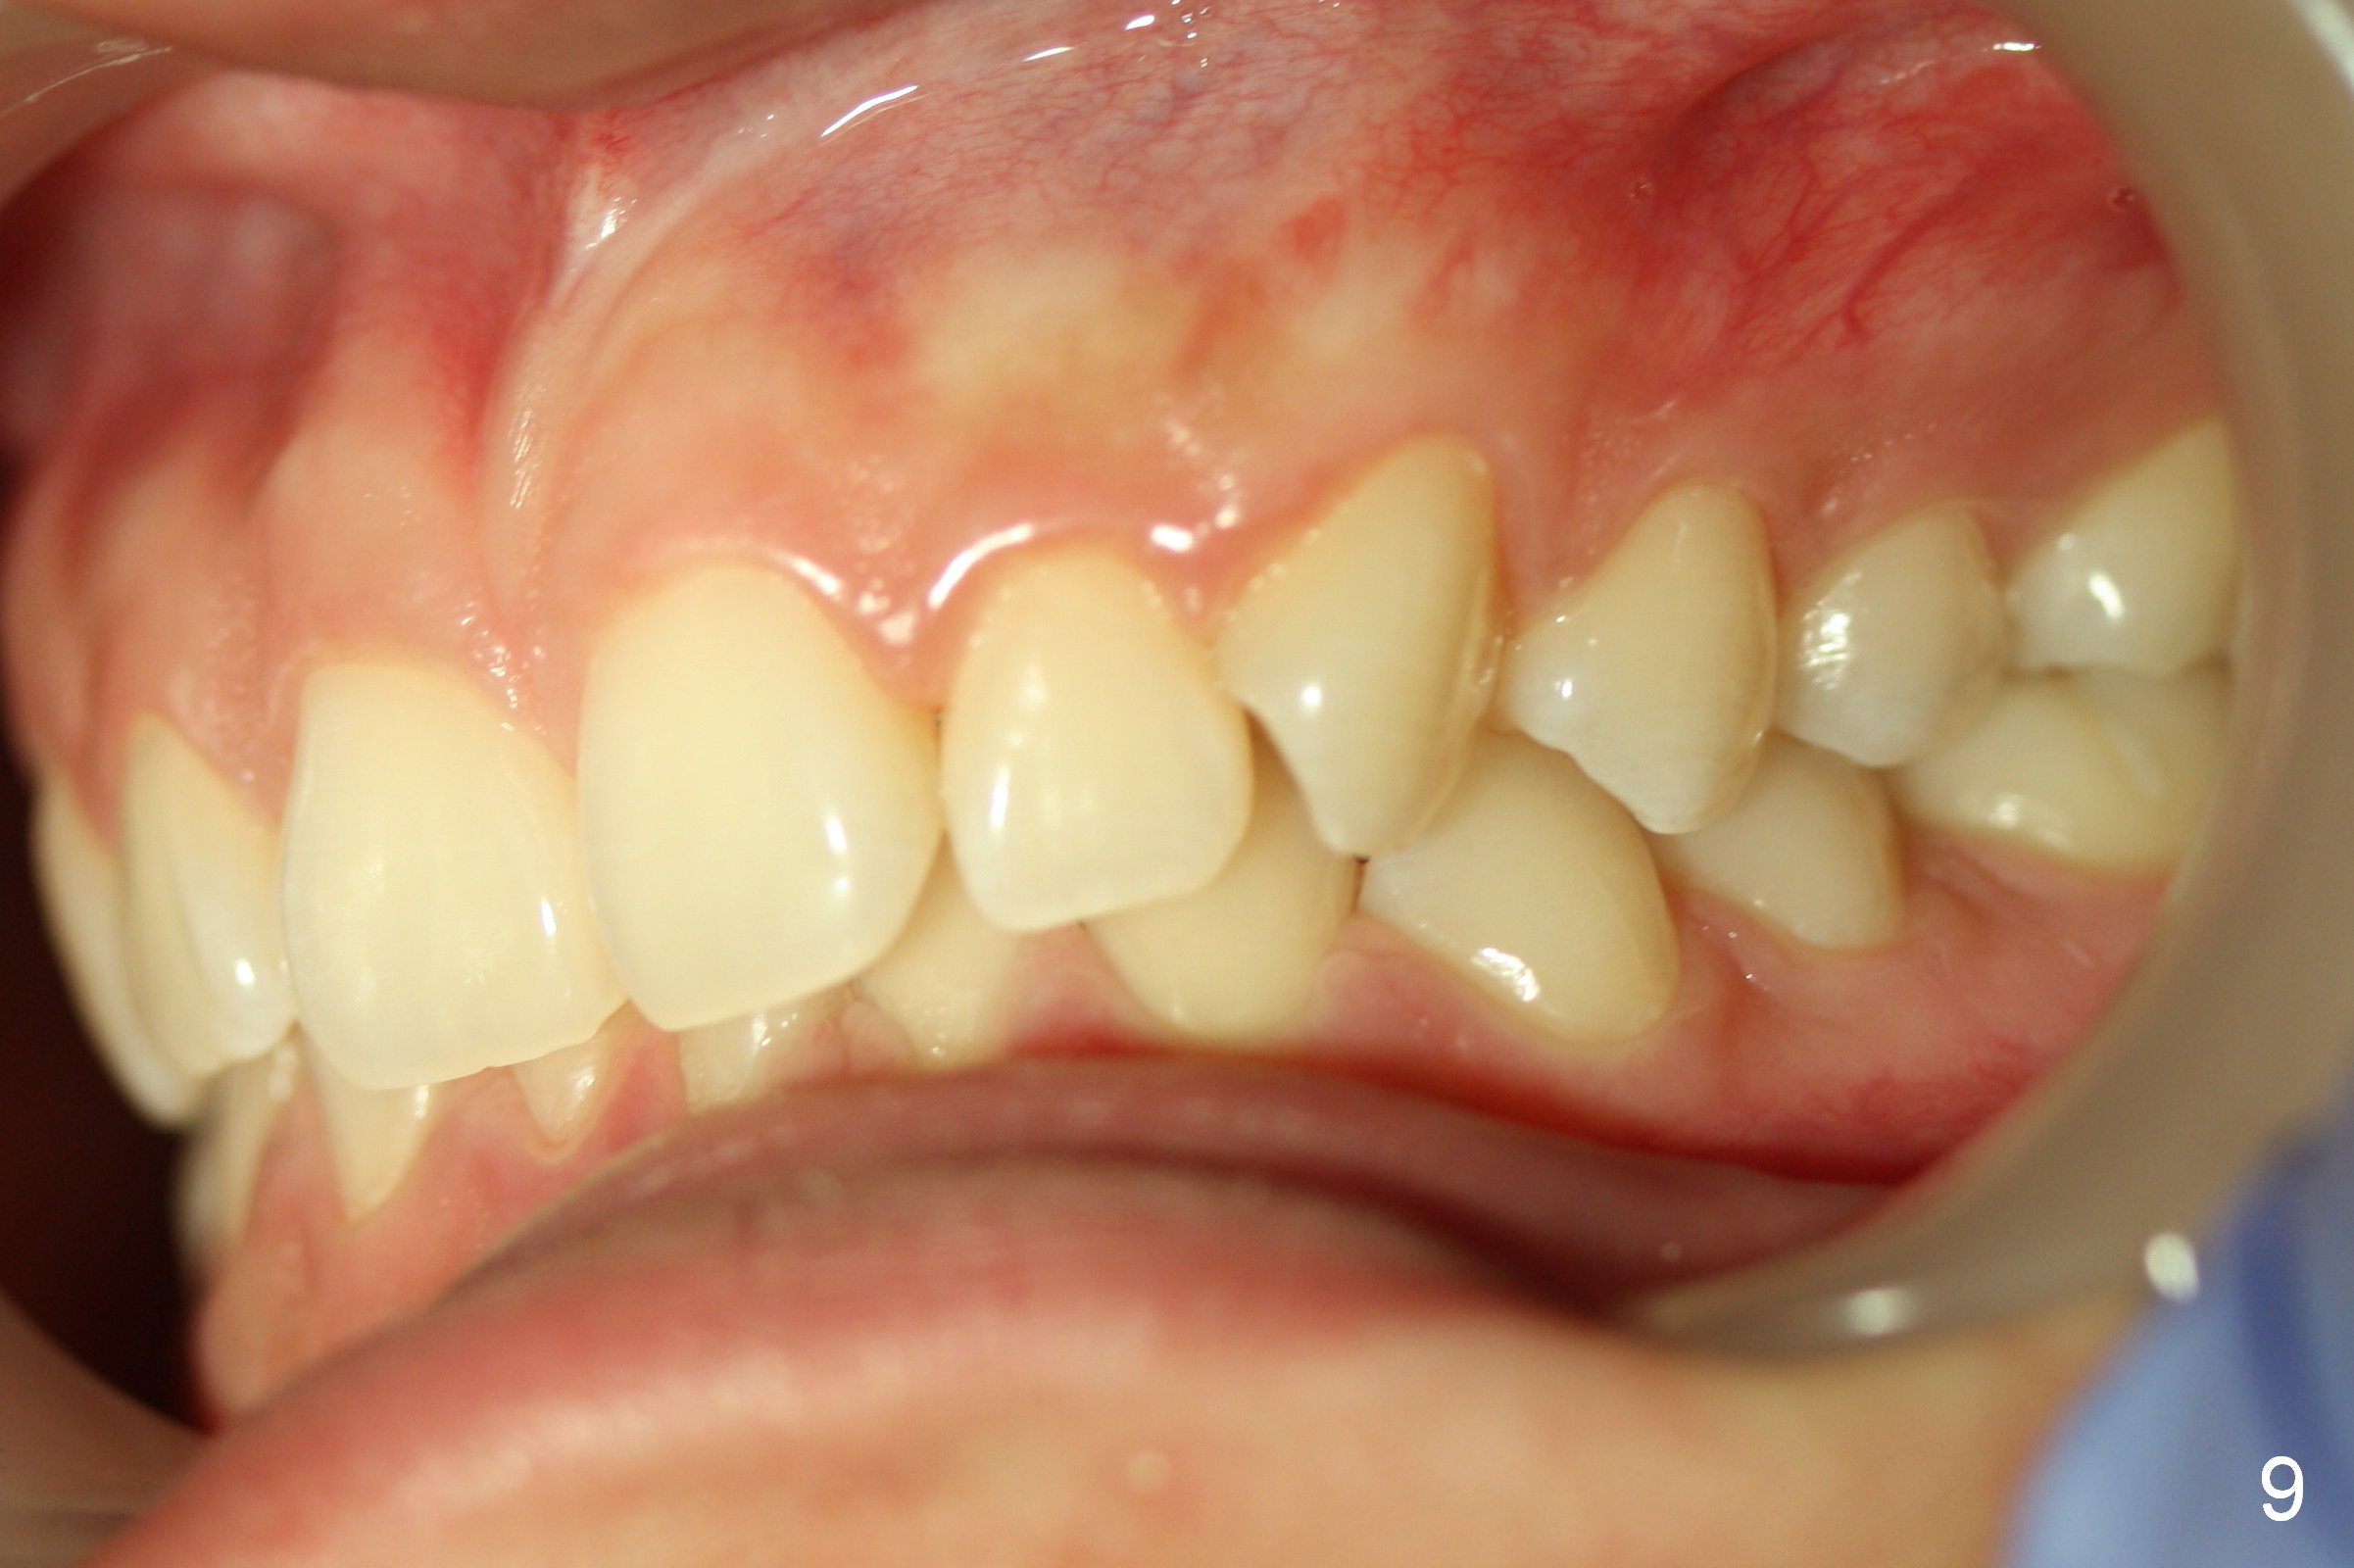

To show the posterior occlusion directly, use the smaller single cheek retractor to retract the corner of the mouth as posterior as possible. For better exposure, ask the patient to hold a mouth mirror lightly at the other corner of the mouth. The camera should be also positioned posteriorly with focus on the region between the canine (mainly) and the 1st molar (as compared to Fig.7 and 9).

To take the anterior view of the occlusion, let the patient turn the head slightly toward you. The camera frame should be parallel to the imaginary occlusal line. When the photo is not straight (Fig.8), it appears that we are unable to set the teeth straight, either.

Jessica is a 15-year-old Chinese. She cares about her upper central incisors and the upper left canine (rotation). Place rotation wedges as early as possible and overcorrect the rotation.